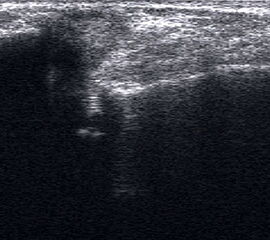

Fibulaverletzung beim Erwachsenen

Fibulafraktur mit Unterbrechung der Kortikalis und Hämatom.

Abbildung 13

Lagerung: Rückenlage, leichte Innrotation des Fußes.

Schnittebene: LS über distaler Fibula.

Referenzstruktur: Fibula im Längsverlauf.

Befunde: Bei einer Außenknöchelfraktur ist eine Unterbrechung der echogenen metaphysären Knochenlinie mit umgebendem flachen, echoarmen periostalen Hämatom zu sehen (Abb.13).

Cave: Ein Os subfibulare kann ebenfalls fälschlicherweise als Fibulaverletzung interpretiert werden!